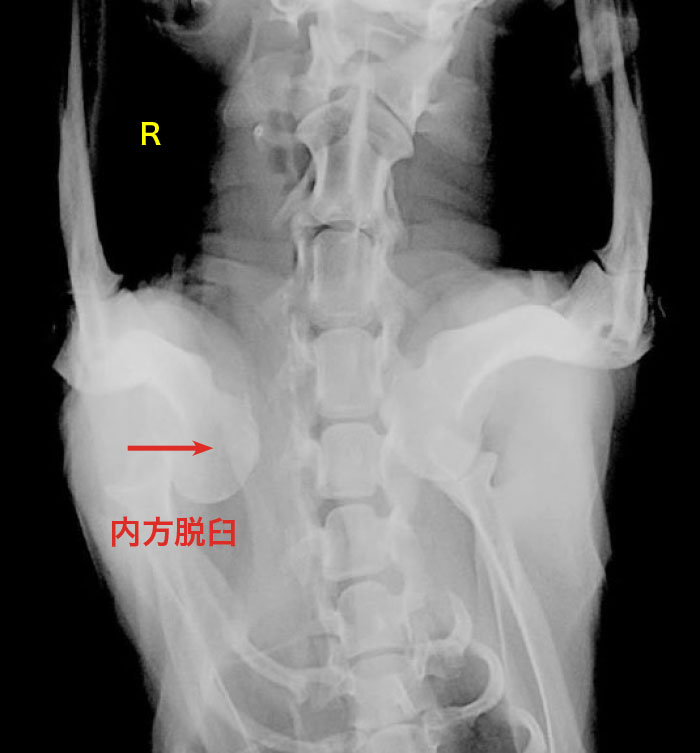

右肩関節内方脱臼